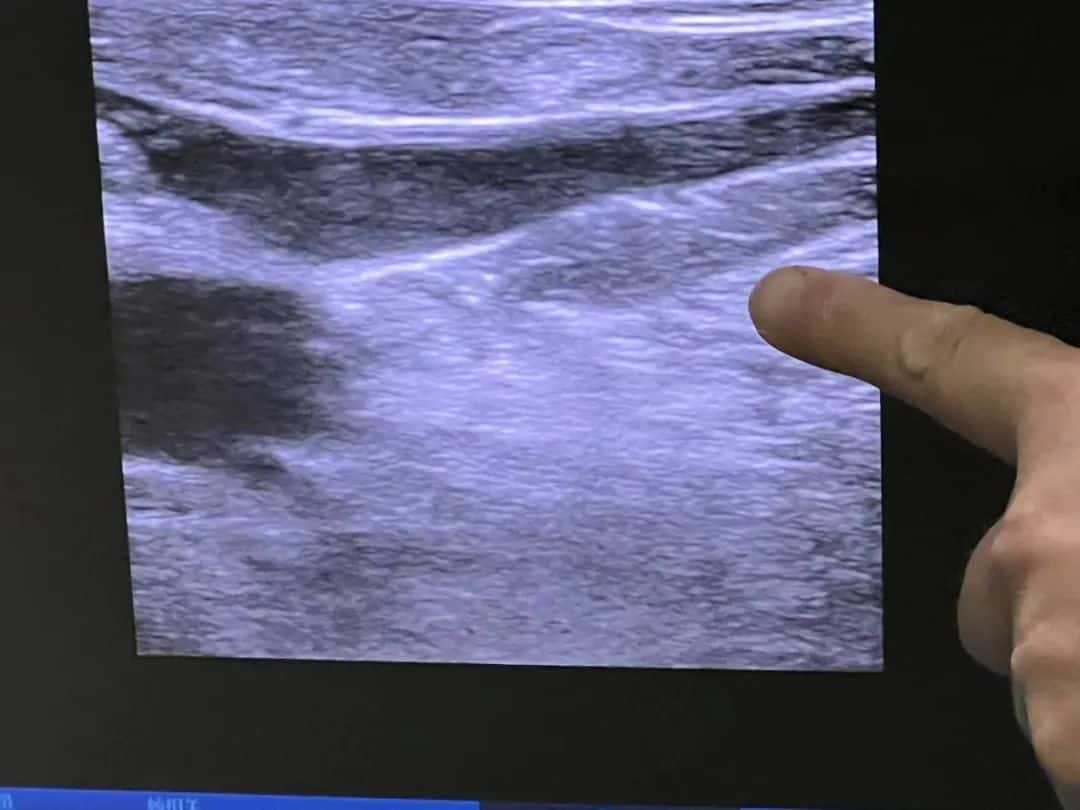

▲消融后股隐交汇处超声图像